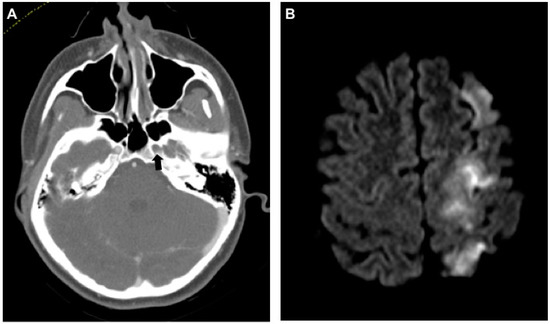

Figure 1. Dissection of the left internal carotid artery (ICA) with severe neurologic sequelae. (A) Axial computed tomography angiogram (CT-A) of the skull base shows no contrast agent in the ICA within the foramen carotideum on the left (black arrow). (B) Same-day magnetic resonance imaging (MRI) (diffusion weighted imaging (DWI), b800) shows ipsilateral infarction of the anterior and middle cerebral artery territories.

The trauma mechanism was a fall from large height in one case (14.3%) and traffic accidents in all other cases (4 car accidents, 1 motor-scooter, 1 e-bike; 85.7%). Concomitant spinal fractures were found in 4 cases (57.1%). One patient had a complex midface fracture reaching into the skull, one patient had no fracture of the spine or thorax (Figure 1). Three patients had fractures of upper third ribs (42.9%).

Third, the most powerful predictor for cervical artery dissections seems to be any kind of high kinetic trauma mechanism, especially traffic accidents including cars, motorcycles/-scooters, bikes, and e-bikes, which is also true for aortic arch injuries due to a “whiplash”-type motion of fast deceleration and re-acceleration [14,15]. Some fractures should raise high suspicion toward cervical artery injuries, such as fractures of the cervical spine, skull base and/or complex midface fractures, or upper third rib (costae 1–4) fractures. Nonetheless, devastating dissections without an accompanying fracture are possible (Figure 1).